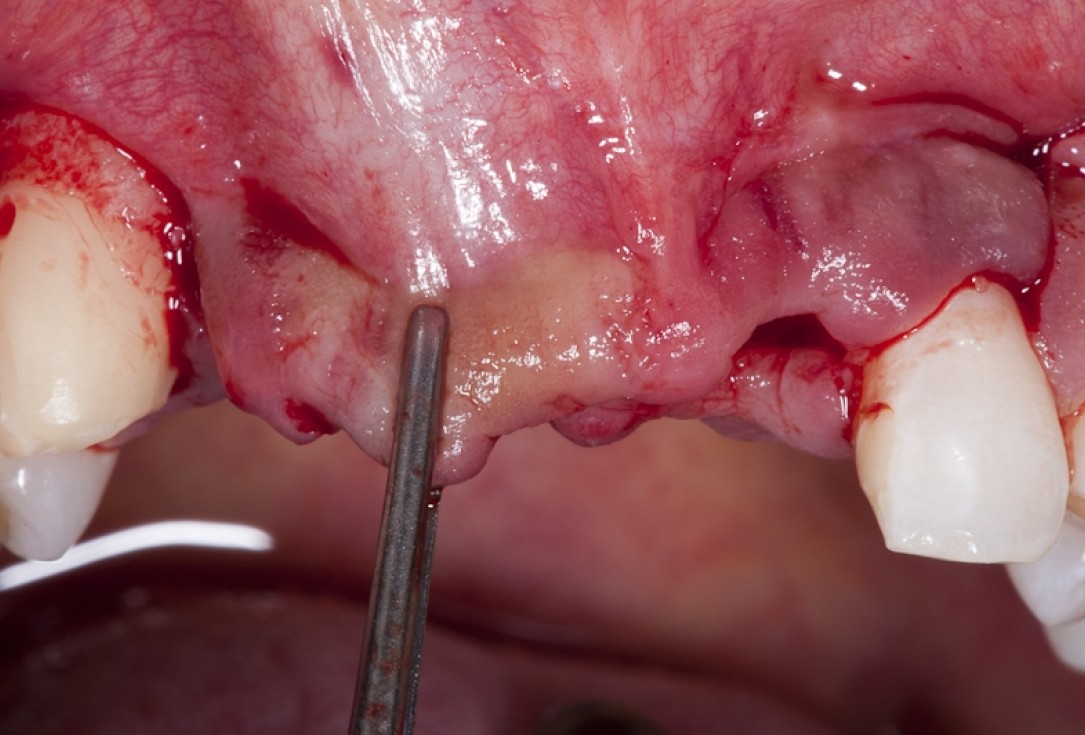

04/17 - Full flap elevation and severe hard tissue exposure

Block augmentation with maxgraft® block & mucoderm® - Dr. K. Chmielewski